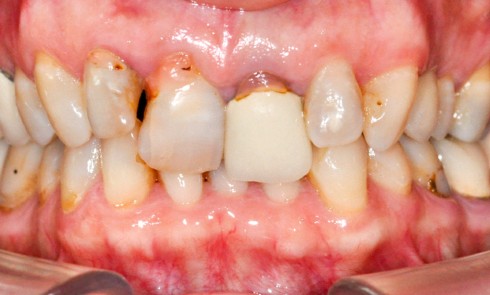

À la suite d’un accident de la voie publique il y a plusieurs années, le secteur antérieur maxillaire a été...